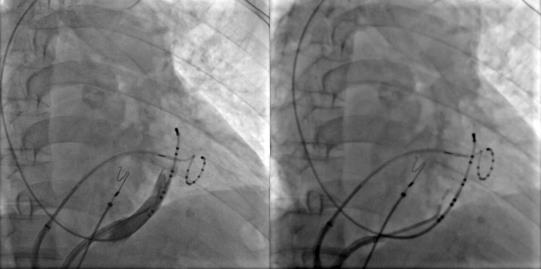

冠状窦造影定位Marshall静脉,应用OTW球囊进行酒精消融

Marshall静脉酒精消融完成后进行左房标测提示二尖瓣峡部彻底隔离,酒精消融成功,接着进行三尖瓣峡部消融后患者房扑转为窦性心律,完美完成此次房颤的消融手术。